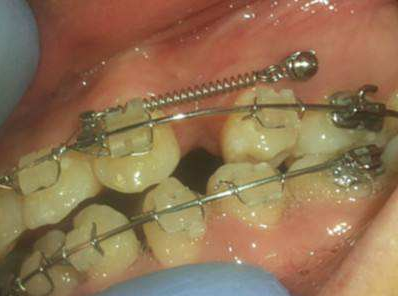

骨釘,顧名思義,是一種外形十分像釘子的種植釘,是放置在牙骨上方一個(gè)迷你的"釘子"。

它體積的小,好植入,近年來(lái),逐漸成為正畸科常用的正畸輔助工具。

可不要看它體積小,卻在多種正畸方案中,成為醫(yī)生的得力助手,扮演著至關(guān)重要的角色

但是有了骨釘植入,就可以解決前者調(diào)節(jié)方案的煩惱,可以根據(jù)不同的調(diào)節(jié)方案,不同的調(diào)節(jié)需求,在口腔中相應(yīng)的位置植入骨釘形成口腔中的一個(gè)受力點(diǎn),同時(shí)利用正畸器,橡皮筋相互拉力的作用下,更好的幫助醫(yī)生更好的控制牙齒的移動(dòng),做到"該移動(dòng)的牙移動(dòng),不該動(dòng)的牙不動(dòng)"從達(dá)到佳的調(diào)節(jié)果。